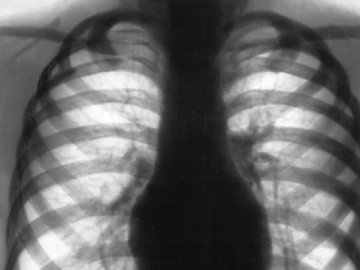

Муковісциоз – важке вроджене генетичне захворювання, при якому порушується обмін речовин в клітинах і організм втрачає можливість виводити слиз. Через це страждають передусім органи дихання: слиз, а з ним і інфекції накопичуються в легенях, людина ризикує захворіти й померти від невиведеної вчасно інфекції, або й просто втрачає можливість дихати.

Муковісциоз – важке вроджене генетичне захворювання, при якому порушується обмін речовин в клітинах і організм втрачає можливість виводити слиз. Через це страждають передусім органи дихання: слиз, а з ним і інфекції накопичуються в легенях, людина ризикує захворіти й померти від невиведеної вчасно інфекції, або й просто втрачає можливість дихати.